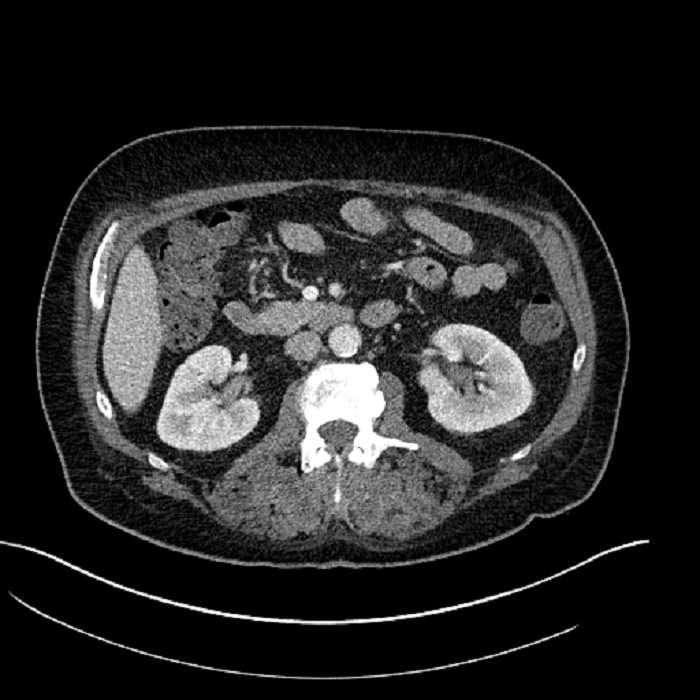

• Mild mural thickening of a segment of the sigmoid colon with adjacent fat stranding and a 1.5 cm fluid and gas collection along the tip of an inflamed diverticulum

• Loss of the normal fat plane between this collection and adjacent loops of small bowel, which demonstrate mural thickening

Acute sigmoid diverticulitis complicated by a small contained perforation and a large abscess in the right hepatic lobe. Additional small subcapsular abscesses along the anterior margin of the left hepatic lobe.

Additionally, loss of the normal fat plane between the peridiverticular collection and adjacent thickened loops of small bowel raises the potential for an enterocolonic fistula.

Hepatic abscess showing the double target sign with low density internally surrounded by a thin inner enhancing rim (red arrow) and ill-defined outer low density rim (yellow arrow). Blue arrow indicates an internal septation. Red arrows: additional smaller subcapsular abscesses. Red arrow: focal contained perforation associated with diverticulitis.